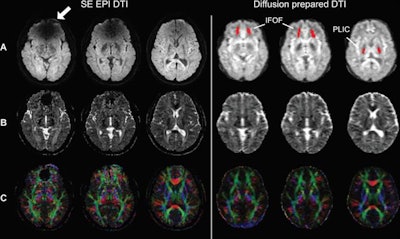

"Susceptibility artifacts caused by metallic objects at echo-planar imaging (EPI) have been a major limitation for functional MRI and diffusion-tensor imaging in participants wearing metallic orthodontic material and other head implants," wrote the authors, led by Xinyuan Miao, PhD, from Johns Hopkins' division of MRI research. "T2-prepared BOLD functional MRI and diffusion-prepared DTI showed preserved signal-to-noise ratio (SNR) in the entire brain, whereas conventional EPI approaches showed significantly reduced SNR in regions with strong susceptibility effects."

In analyzing the results, Miao and colleagues found that T2-prepared BOLD fMRI and 3D diffusion-prepared DTI with 3D fast GRE both outperformed EPI for signal-to-noise ratio in the entire brain, which resulted in much better image quality. T2-prepared BOLD fMRI also significantly bested conventional EPI in contrast-to-noise ratio in regions with strong susceptibility to metal braces.

Since a picture is worth a thousand words, the researchers also observed much better results with diffusion-prepared DTI with 3D fast GRE, compared with spin-echo EPI DTI.

"Our results showed that T2-prepared blood oxygenation level-dependent functional MRI and diffusion-prepared diffusion tensor imaging can be useful alternatives for human brain mapping when echo-planar imaging fails to provide robust signals in the presence of metallic implants such as dental braces," Miao and colleagues concluded.